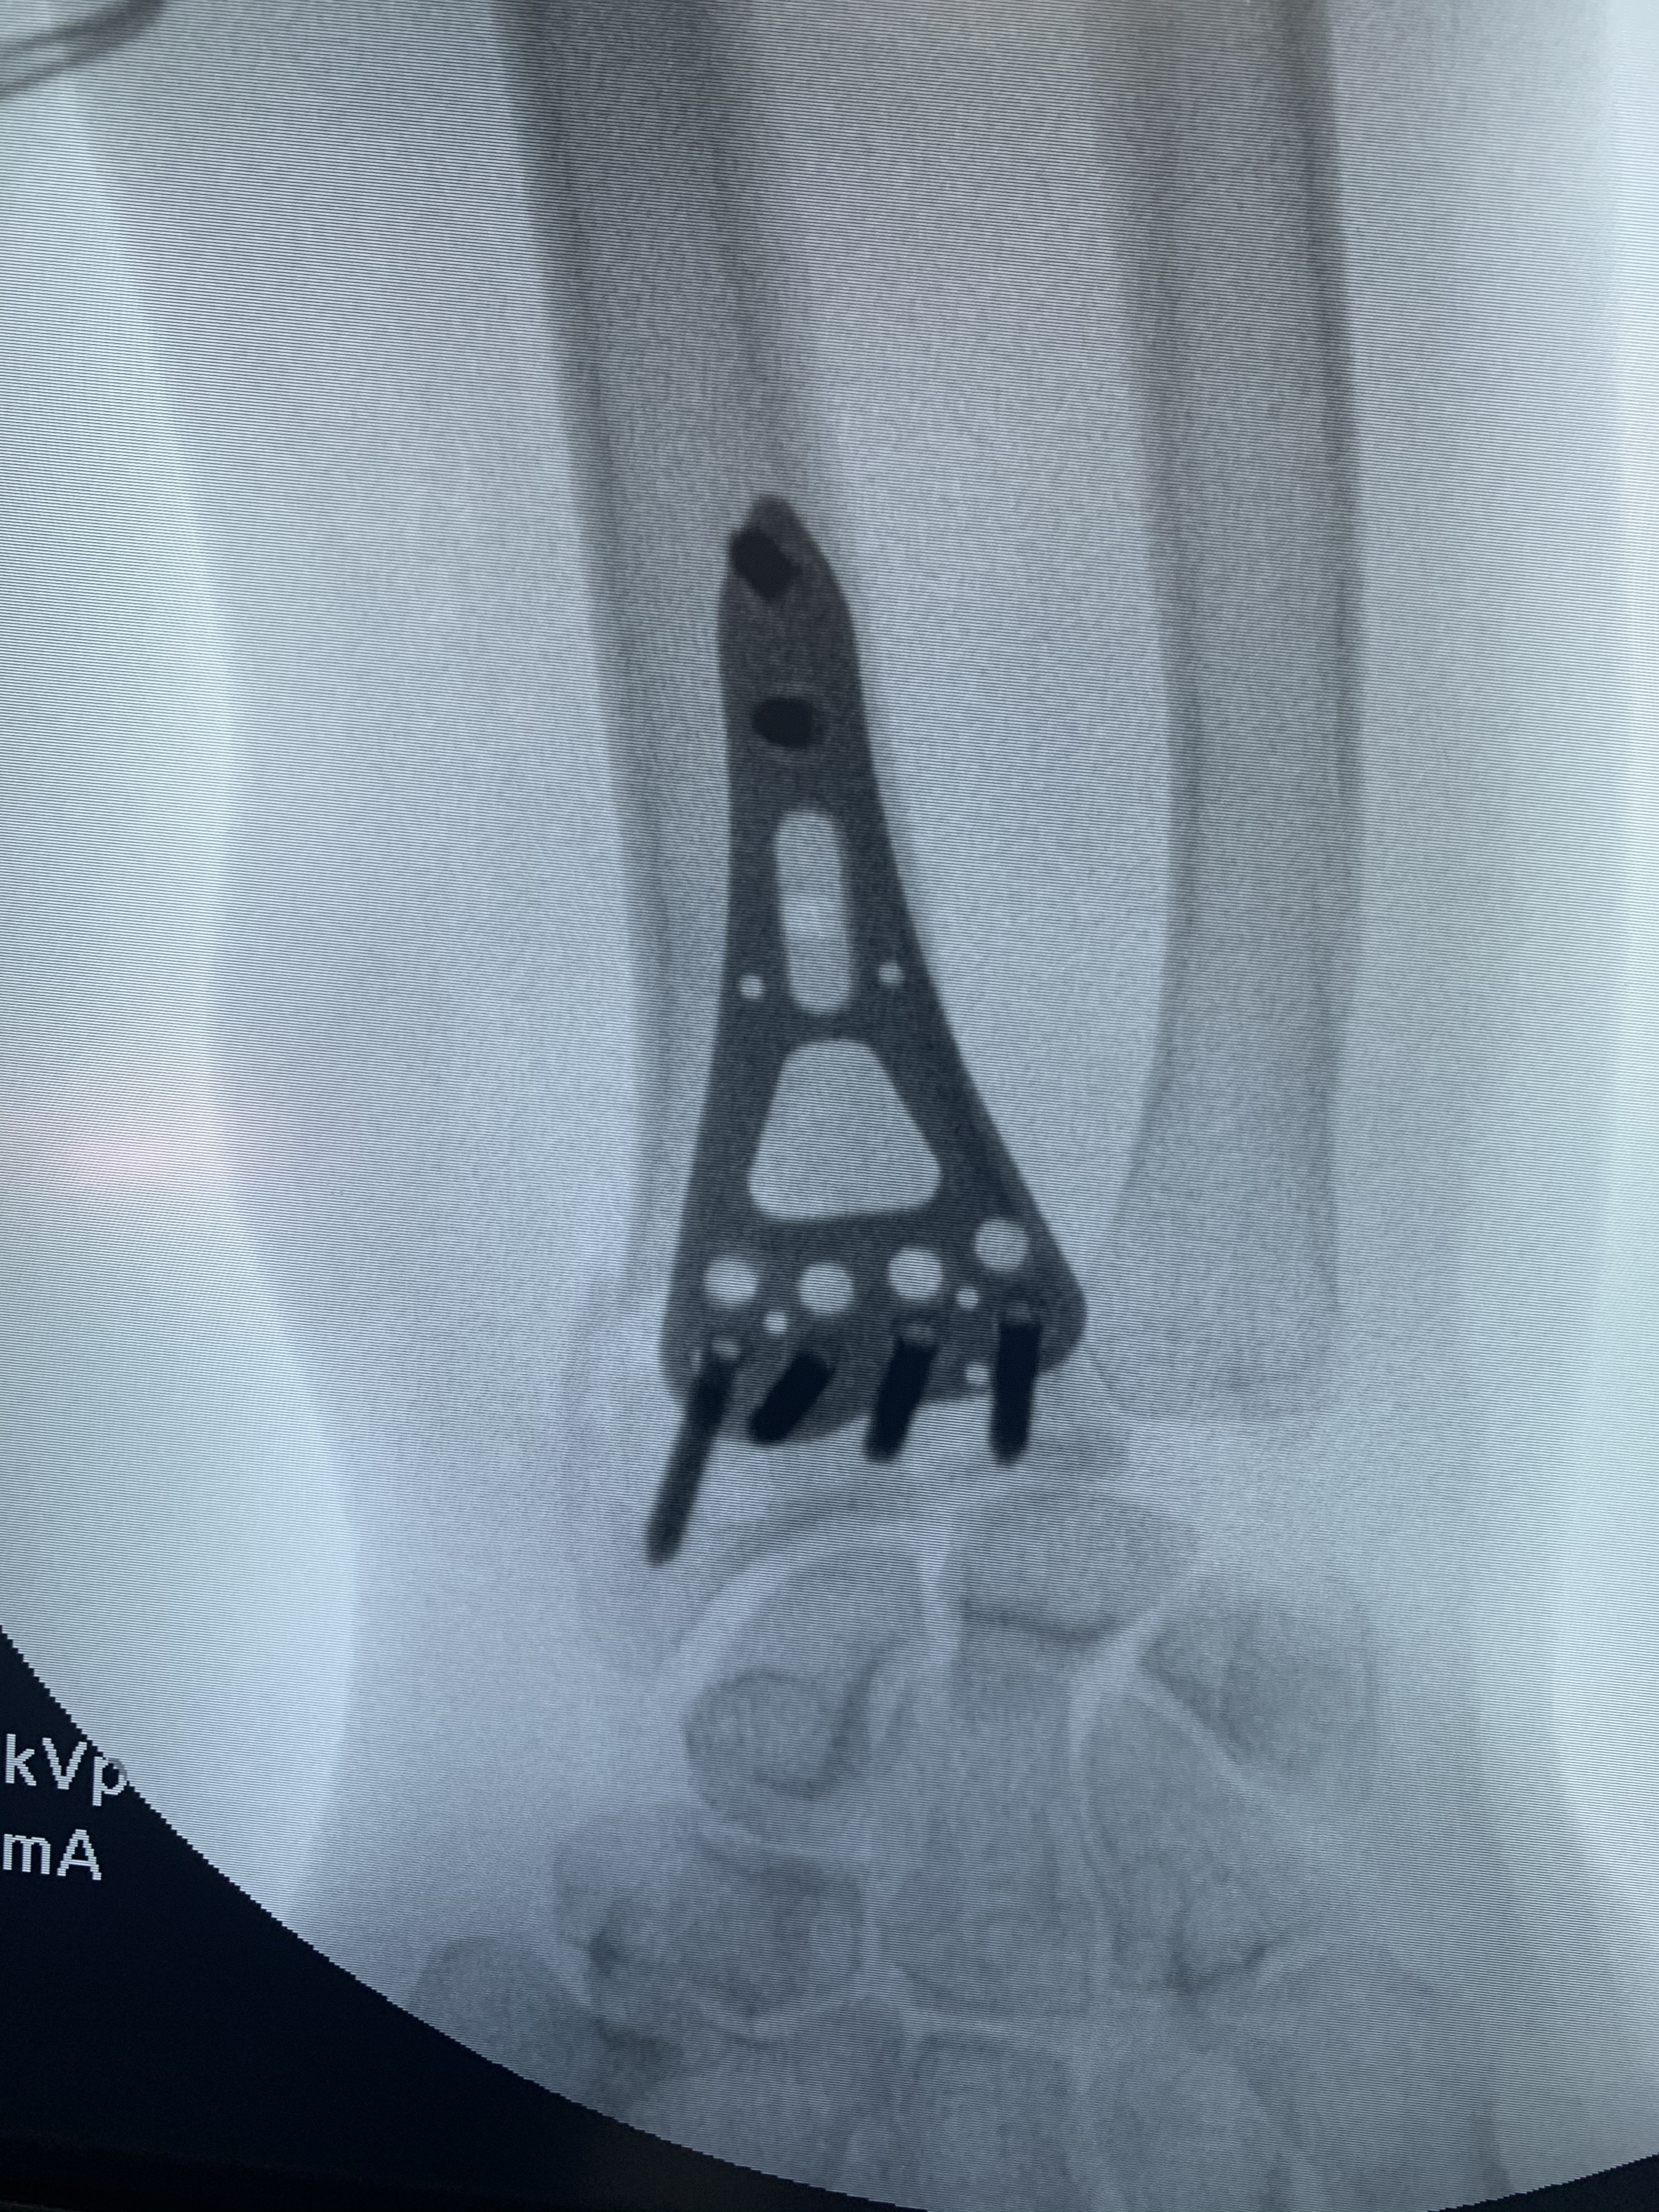

Galería de fotos clínica, servicios, cirugías, casos de pacientes Visítenos, ambiente limpio, agradable y seguro. Trabajando Operando en tiempos de coronavirus Dr Barquero Traumatologo Compartir en X (Se abre en una ventana nueva) X Comparte en Facebook (Se abre en una ventana nueva) Facebook Imprimir (Se abre en una ventana nueva) Imprimir Compartir en WhatsApp (Se abre en una ventana nueva) WhatsApp Enviar un enlace a un amigo por correo electrónico (Se abre en una ventana nueva) Correo electrónico Me gusta Cargando...